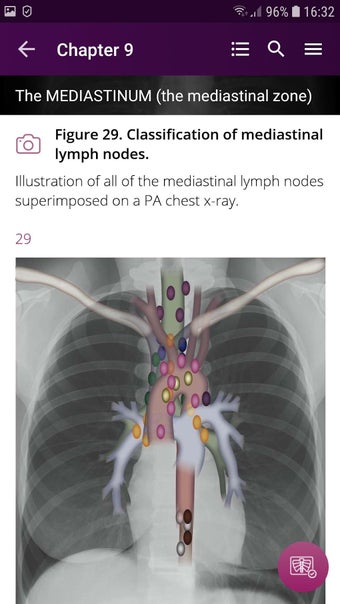

Radioloji'yi Keşfet: Göğüs Röntgeni Yorumlama, göğüs röntgeninin yorumlanmasının anlaşılmasını artırmak için tasarlanmış bir eğitim uygulamasıdır ve doktorlar, tıp öğrencileri ve radyologlar tarafından kullanılması amaçlanmaktadır. Uygulama, en küçük detayları görüntülemek için yakınlaştırılabilecek yüksek kaliteli görüntüler ve her bulgunun önemini anlamanıza yardımcı olacak bir sesli yorum içerir.

Uygulamanın amacı, kullanıcıların farklı x-ışını bulgularını ve bunların bir hastalığın teşhisinde nasıl kullanılabileceğini daha iyi anlamalarına yardımcı olmaktır. Uygulama, göğüs röntgeni yorumlaması için gerekli çeşitli yapı taşlarını kapsayan 5 bölüme ayrılmıştır.